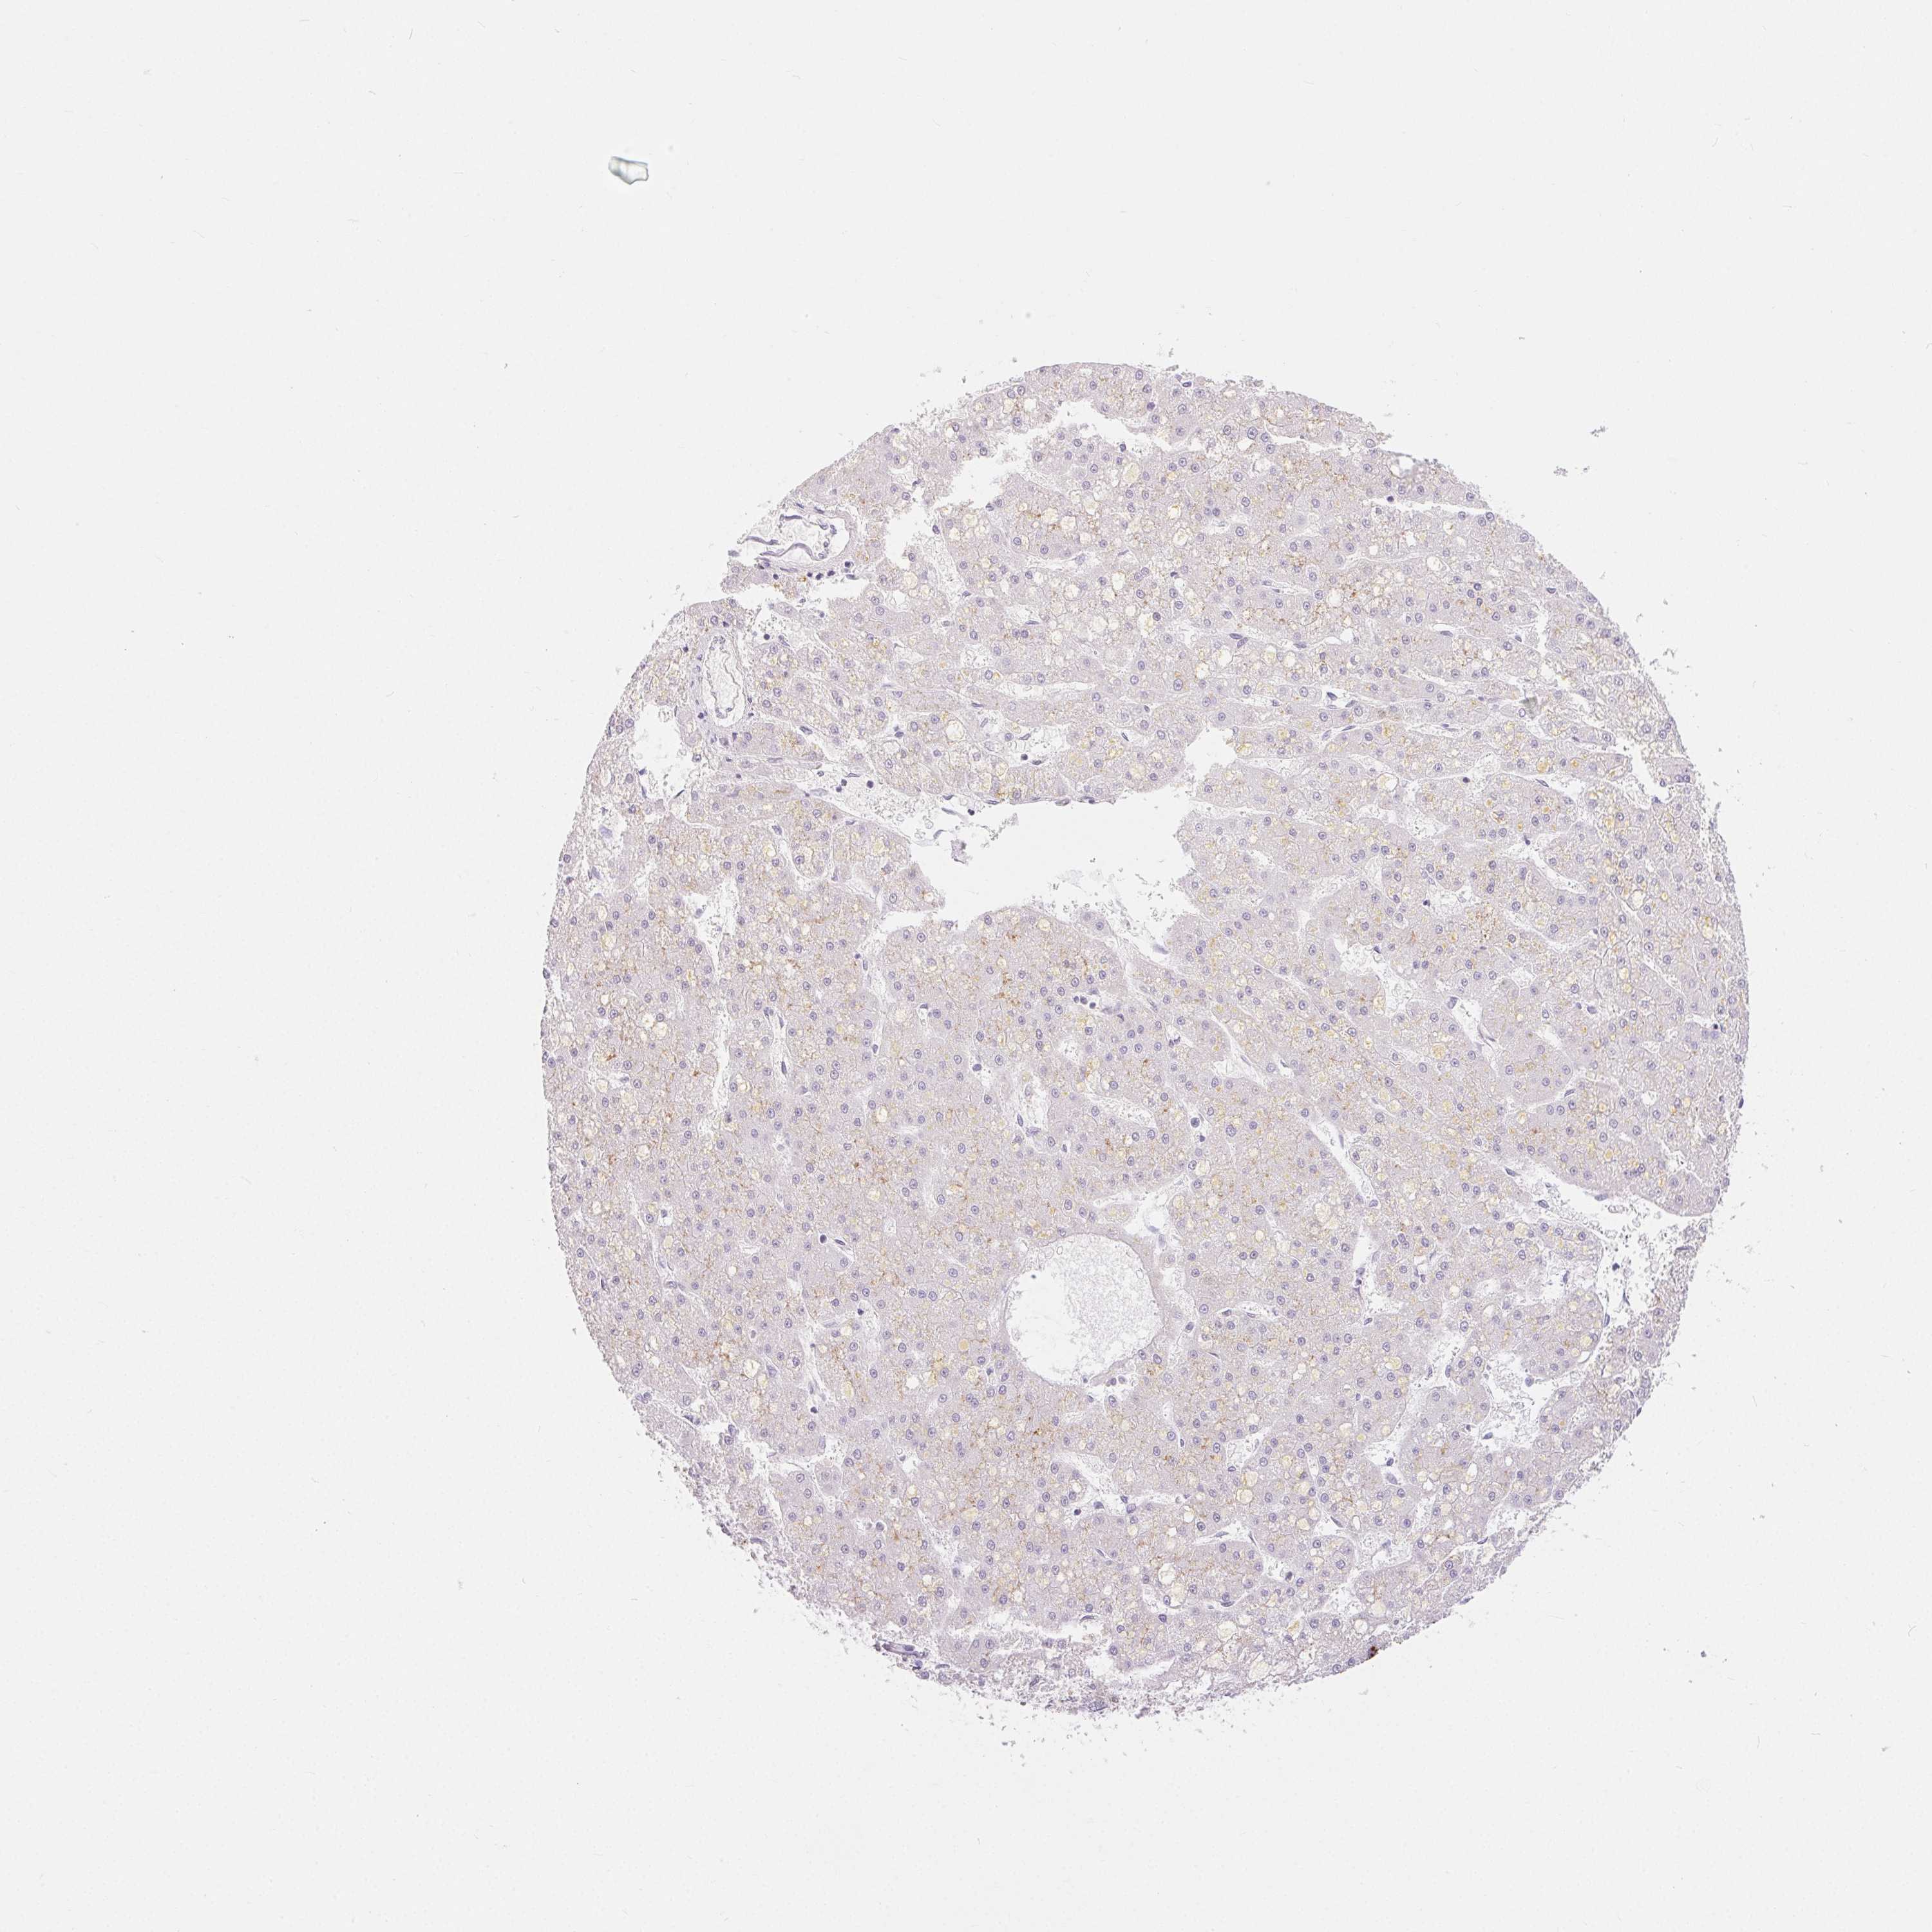

LIVER CANCER - Protein expressioni

A mouse-over function shows sample information and annotation data. Click on an image to view it in a full screen mode. Samples can be filtered based on level of antibody staining by selecting one or several of the following categories: high, medium, low and not detected. The assay and annotation is described here.

Note that samples used for immunohistochemistry by the Human Protein Atlas do not correspond to samples in the TCGA dataset.

Antibody stainingi

Antibody staining in the annotated cell types in the current human tissue is reported as not detected, low, medium, or high, based on conventional immunohistochemistry profiling in selected tissues. This score is based on the combination of the staining intensity and fraction of stained cells.

Each image is clickable and will lead to virtual microscopy that enables deeper exploration of all samples and also displays staining intensity scores, fraction scores and subcellular localization as well as patient and tissue information for each sample.

Antibody HPA016843

Antibody CAB034017

Staining

High

Medium

Low

Not detected

Intensity

Strong

Moderate

Weak

Negative

Quantity

>75%

75%-25%

<25%

None

Location

Nuclear

Cytoplasmic/membranous

Cytoplasmic/membranous,nuclear

Carcinoma, Hepatocellular, NOS

Cholangiocarcinoma